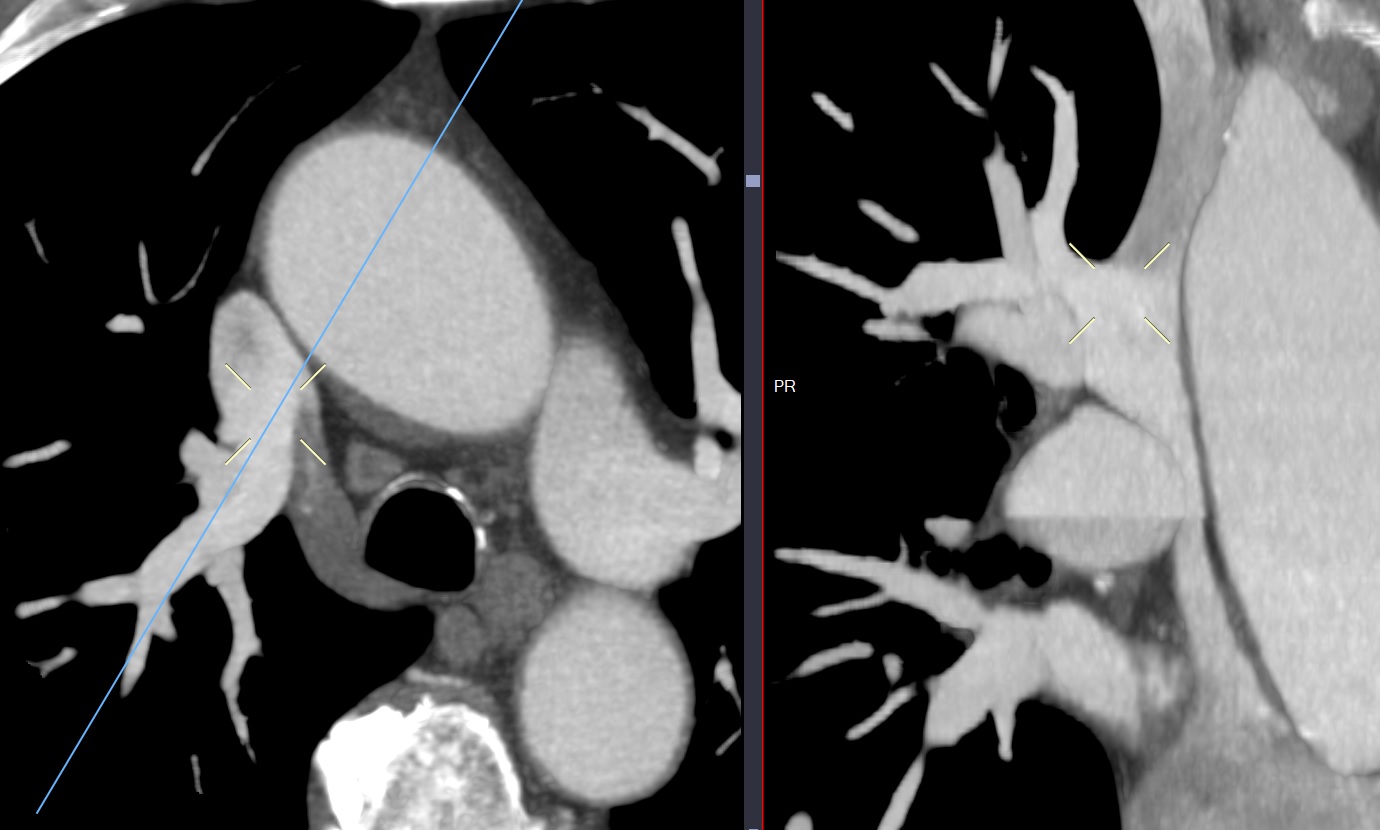

Retour veineux pulmonaire anormal partiel

les veines pulmonaires supérieures droites Dans la VCS

les veines pulmonaires supérieures droites Dans la VCS